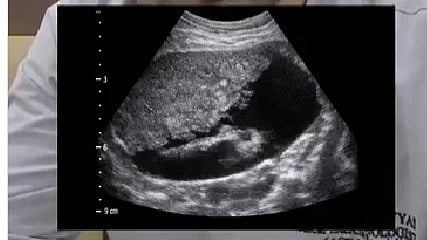

A preventive and diagnostic radiologist, Dr. Harsh Vyas, shared an ultrasound image of a 28-year-old man diagnosed with advanced and irreversible liver cirrhosis, even though the patient reportedly consumed alcohol only occasionally. The image and accompanying caption were posted to Dr. Vyas’s Instagram account on December 27, 2025, sparking public attention to liver disease risk factors.

In his social media post, Dr. Vyas explained that the ultrasound (USG) imaging revealed signs consistent with liver cirrhosis, a condition where healthy liver tissue is replaced by scar tissue (fibrosis) and the organ’s structure and function are significantly impaired. The scan also showed ascites, excess fluid accumulation in the abdominal cavity often seen in advanced liver disease and associated with complications such as pain and swelling.

Medical literature notes that early liver injury can occur without clear symptoms, and routine testing such as liver function tests (LFTs) and imaging like ultrasound or FibroScan can detect early structural changes; advanced cirrhosis typically exhibits structural distortion on imaging.